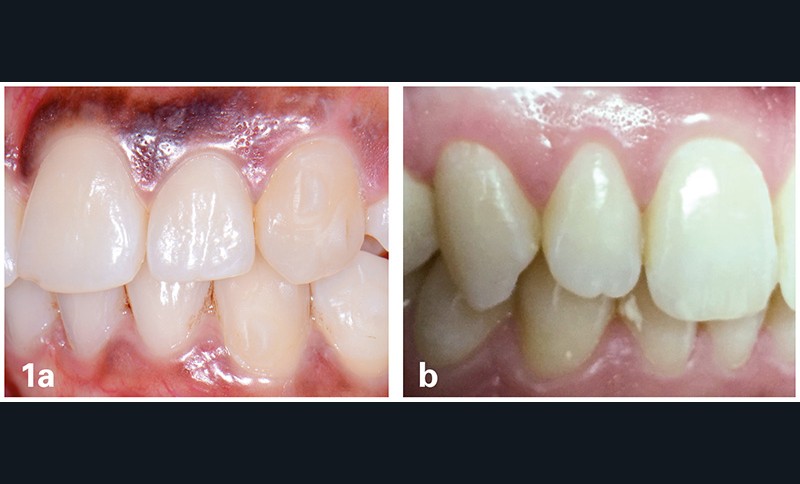

– soit une ligne courbe telle que la limite gingivale de l’incisive latérale soit juste coronaire à l’incisive centrale et à la canine adjacentes (fig. 1a) ;

– soit une ligne droite telle que les limites gingivales des incisives centrale et latérale et de la canine soient au même niveau (fig. 1b).